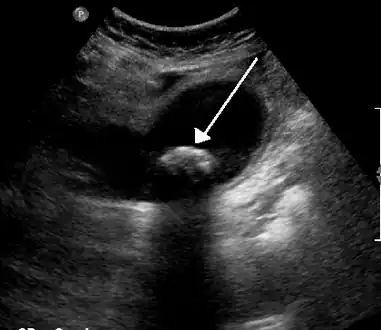

Diagnosis

Diagnosis is typically confirmed by abdominal ultrasound. Other imaging techniques used are ERCP and MRCP. Gallstone complications may be detected on blood tests.[2]

On abdominal ultrasound, sinking gallstones usually have posterior acoustic shadowing. In floating gallstones, reverberation echoes (or comet-tail artifact) is seen instead in a clinical condition called adenomyomatosis. Another sign is wall-echo-shadow (WES) triad (or double-arc shadow) which is also characteristic of gallstones.[38]